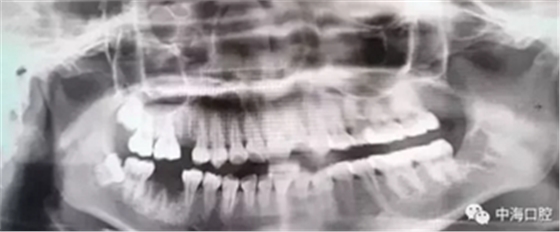

下面這兩張圖,據(jù)說拔牙費(fèi)時1.5小時,收費(fèi)14000元。